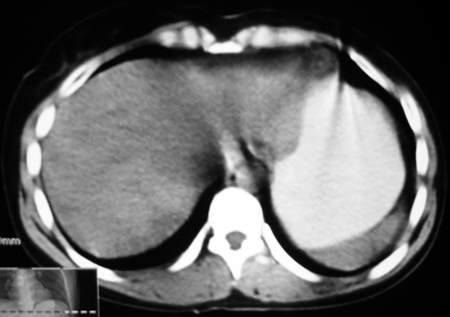

以下是引用bmw011在2009-4-23 13:28:00的发言:[br]考虑右肾包膜下血肿。

以下是引用卜一在2009-4-23 15:43:00的发言:[br]考虑右肾包膜下血肿,不排除占位病变伴出血可能,建议进一步检查。